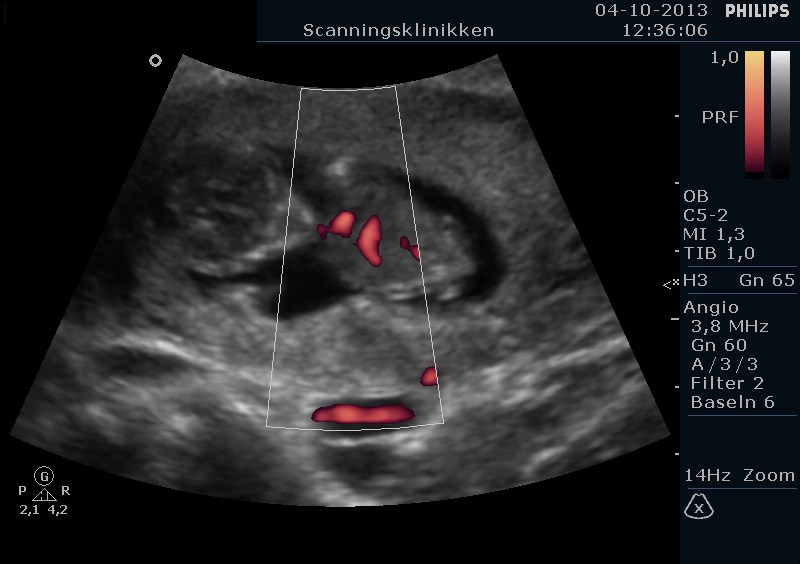

Men se lige hvad vi har set i dag. En lille spire på næsten 5 cm og er 11+5 uger henne med en termin den 20 April <3